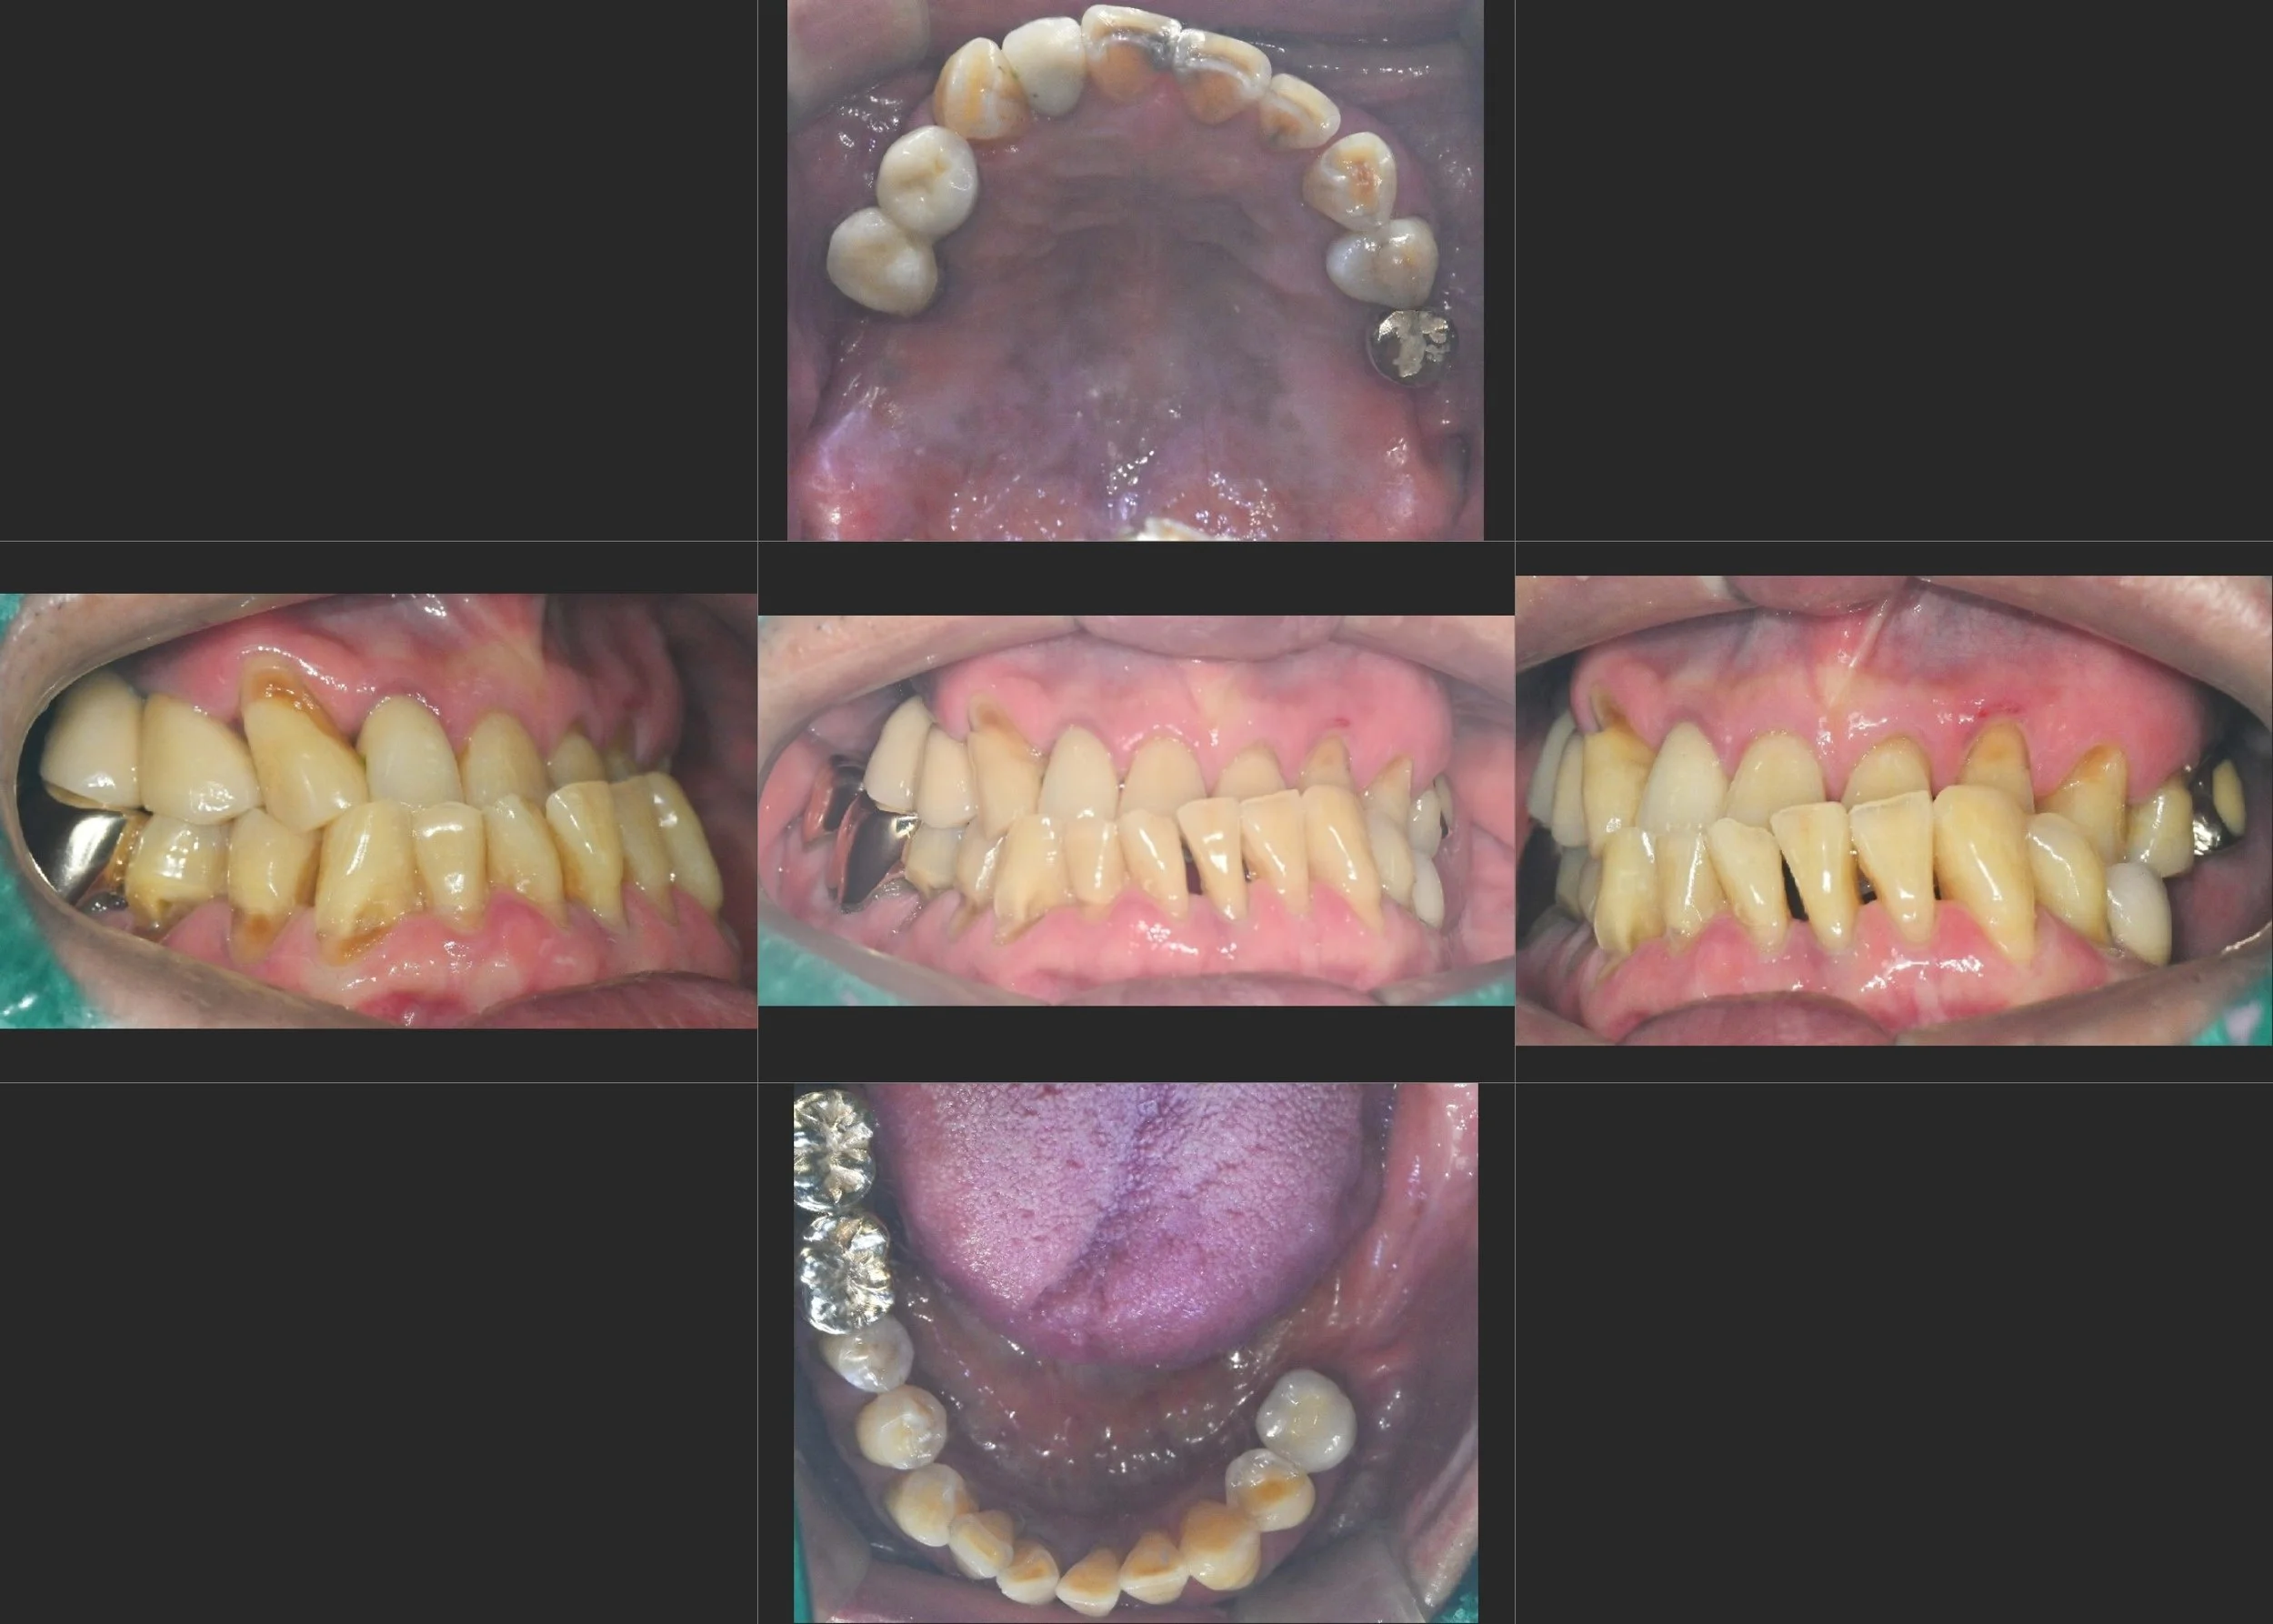

38. Comprehensive Full-Arch Reconstruction: Reversing the Domino Effect of Tooth Loss

Management of Generalized Severe Periodontitis and Posterior Bite Collapse in a Female Patient in her 60s. A Systematic Approach to VDO Recovery and Strategic Esthetic Rejuvenation.